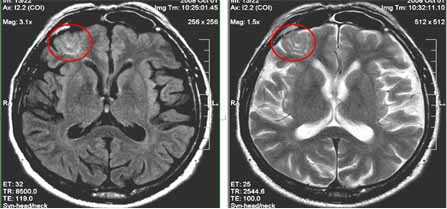

5. МР-картина узловой субкортикальной гетеротопии левой лобно-теменной области.

В первом случае визуализируются узлы гетеротопии в субкортикальных отделах белого вещества парасагиттальных отделов левой лобно-теменной области.

На втором скане - единичный мелкий узел гетеротопии в белом веществе правой лобной доли (характеристики МР-сигнала идентичны серому веществу головного мозга)

На третьем изображении - множественные узлы гетеротопии вдоль стенок переднего рога левого бокового желудочка и задних рогов обоих желудочков (характеристики МР-сигнала узлов идентичны серому веществу головного мозга)

6. МР-картина перестройки серого вещества правой лобной доли (характерно для фокальной кортикальной дисплазии).

Участок перестройки структуры серого вещества правой средней лобной извилины с утолщением серого вещества и визуализацией дополнительных мелких извилин и участков линейного глиоза.